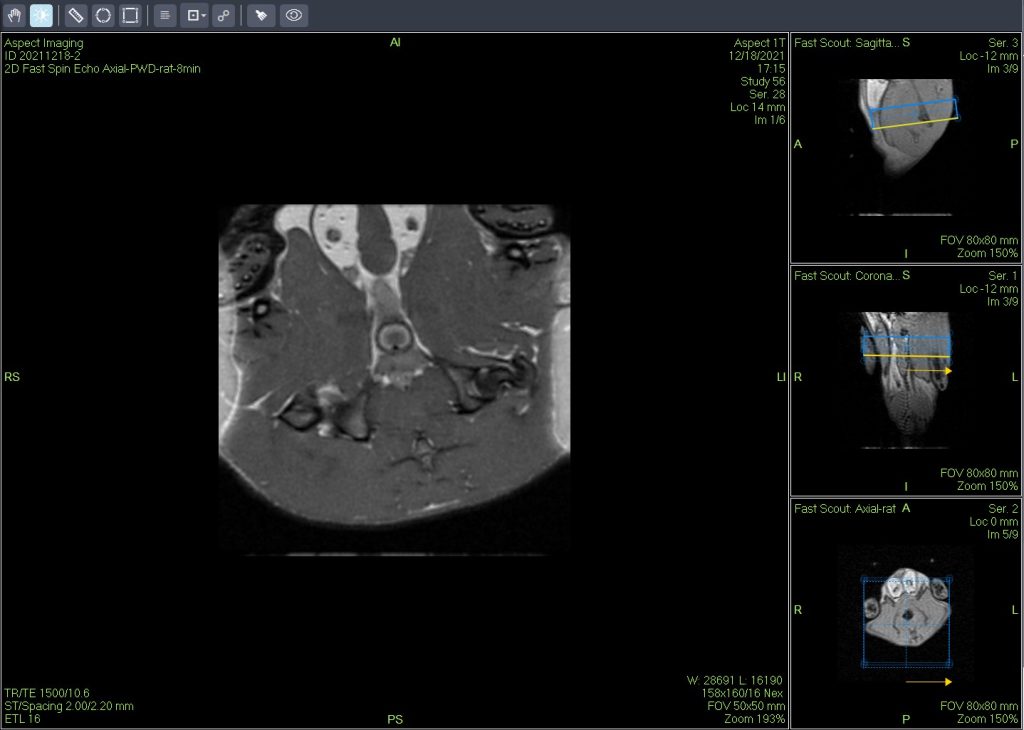

Dixon序列用于大鼠、小鼠水脂分离磁共振成像-脂肪抑制技术

Dixon脂肪抑制技术是由Dixon 提出,其基本原理是利用水、脂肪的化学位移差异,使用不同的回波时问,分别采集水和脂肪质子的in Phase 和 opposed -phase两种回波信号。

使用仪器: 小动物核磁共振成像仪NM21-040H-I 小动物核磁共振成像仪NM20-060H-I 小动物核磁共振成像仪NM42-040H-I